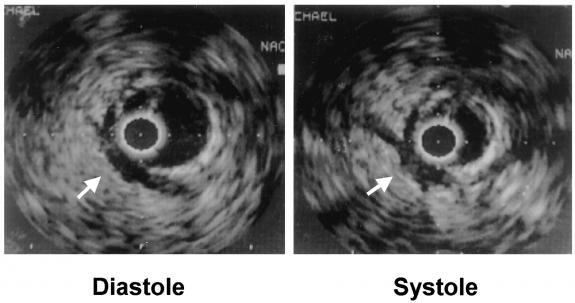

IVUS-images of the myocardial bridge during diastole (left) and systole (right). A “half-moon”–like area surrounding the tunneled segment is present during the entire cardiac cycle.

On IVUS, there are specific signs that are characteristic of bridging and include a specific, echolucent half-moon phenomenon over the bridge segment, which exists throughout the cardiac cycle; accelerated flow velocity at early diastole (the part of the cardiac cycle when the heart is refilled with blood) (fingertip phenomenon).